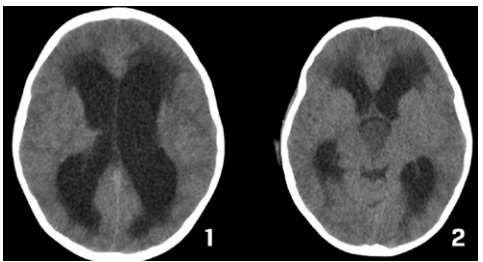

Criança feminina, 04 anos, é encaminhada de Unidade de Pronto Atendimento (UPA) de Olinda-PE com história de cefaleia acompanhada de vômitos, inapetência e sonolência há 03 dias, sendo solicitado parecer da neurocirurgia. Ao exame: ECG Pediátrica de 13 (Resposta Ocular = 3 + Resposta Verbal = 4 + Resposta Motora = 6), isocórica e RFM lentificado bilateralmente, mobilizando todos os membros e reflexos presentes e simétricos.

Seguem, abaixo, as imagens de TC de crânio sem e com contraste da paciente, com índice de Evans de 0,41.

Pelas imagens mostradas, qual o mais provável diagnóstico e o objetivo do tratamento para a paciente?